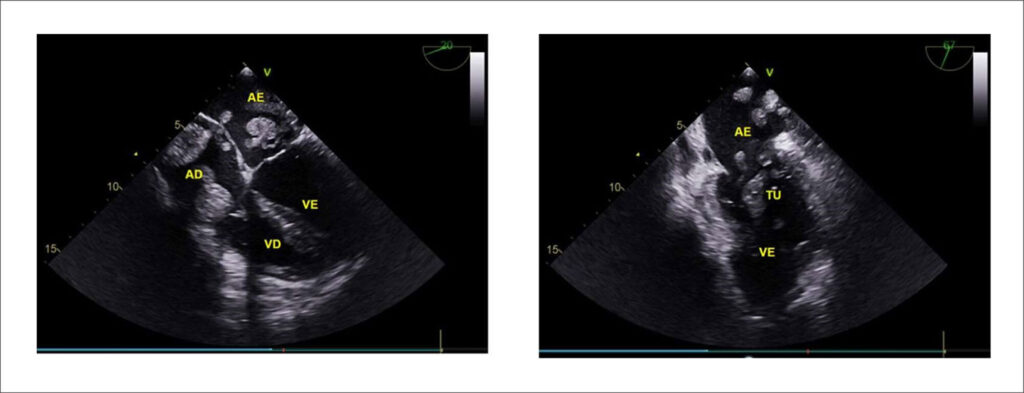

Metástase Cardíaca e Tumor Ovariano de Krukenberg: Um Relato de Caso

Os tumores cardíacos primários são raros, apresentando incidência de 0,0017% a 0,28%. Os tumores secundários ou metastáticos, em contrapartida, são 40 a 100 vezes mais frequentes que os primários. Os sítios primários que metastatizam com maior frequência para o coração são pulmão, mama, melanoma maligno e tumores hematológicos. Metástase cardíaca secundária a tumores ovarianos é infrequente e, nos casos descritos, acomete principalmente pericárdio, sem descrição de lesões intracavitárias. As neoplasias metastáticas podem alcançar o coração pelas seguintes vias: hematogênica, extensão direta, vasos linfáticos, e através das veias pulmonares e da veia cava.,

O termo “tumor de Krukenberg” é utilizado clinicamente para designar um carcinoma metastático de células em anel de sinete, secretor de mucina no denso estroma fibroblástico do ovário. Acomete principalmente mulheres na pré-menopausa, sendo a idade média de diagnóstico 45 anos, e tem como sítio primário mais comum o estômago, responsável por 70% dos casos, seguido de cólon, apêndice e mama., A história de carcinoma prévio ao diagnóstico do Krukenberg é obtida em apenas 20% dos casos, sendo o sítio primário, muitas vezes, desconhecido. A taxa de mortalidade é elevada, com sobrevida média de 14 meses após o diagnóstico.,